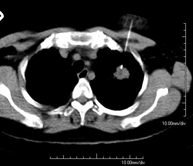

- TC Tórax

Prueba diagnóstica que consiste en obtener imágenes del tórax de alta definición anatómica (pulmones, corazón, mediastino, grandes vasos, caja torácica, etc.) mediante el empleo de un equipo de TC (Tomografía Computarizada). Dichas imágenes se estudian posteriormente en una estación de trabajo que permite reconstrucciones bidimendionales en diferentes planos del espacio y también reconstrucciones 3D (volumétricas). Algunos estudios requieren el empleo de contraste yodado para mejorar la definición de las imágenes. - Angio-TC Aorta torácica

Prueba diagnóstica que consiste en el estudio de la aorta torácica (principal arteria del tórax) mediante el empleo de un equipo de TC (Tomografía Computarizada). Esta técnica requiere el empleo de contraste yodado, y proporciona imágenes de alta definición anatómica. El uso del TCMD (TC Multidetector) acorta el tiempo de exploración, disminuye la dosis de radiación y mejora la calidad de la imagen. Gracias a los múltiples detectores, en determinados estudios se puede acoplar la obtención de la imagen con el latido cardíaco, técnica que permite el estudio de la válvula aórtica y de la raíz de la arteria aorta (primeros centímetros), donde el latido del corazón suele provocar múltiples artefactos de movimiento. - Angio –TC Artèries pulmonars (estudi TEP, Tromboembòlia pulmonar)

Prova que consisteix en obtenir una mostra de teixit de lesions toràciques, com per exemple masses pulmonars, mediastíniques, lesions òssies, etc. Per això s'administra anestèsia local sobre la zona de punció, que es realitza amb agulles de calibre fi. Tot el procediment es realitza controlat amb imatges obtingudes per tomografia computaritzada (TC) en diversos moments de la punció, mitjançant un equip de Fluoroscòpia-TC. Després de la prova, el pacient resta unes hores hospitalitzat. És necessari portar proves de coagulació abans de la punció. - Biòpsia tòrax guiada per TC

Consisteix en obtenir una mostra de teixit d'una determinada lesió toràcica, com per exemple del pulmó, del mediastí, de l'estern, etc. A vegades es realitza sota sedació, amb l'ajuda de l'equip d'anestèsia. S'utilitzen agulles que permeten l'obtenció d'un cilindre de la lesió a estudiar que s'enviarà a Anatomia Patològica per a la seva anàlisi histològica. Tot el procediment es realitza controlat amb imatges obtingudes per tomografia computaritzada (TC) en diversos moments de la biòpsia, mitjançant un equip de Fluoroscòpia-TC. Després de la prova, el pacient resta hospitalitzat per controlar la seva evolució. És necessari portar proves de coagulació abans de la punció. - TC Columna Dorsal